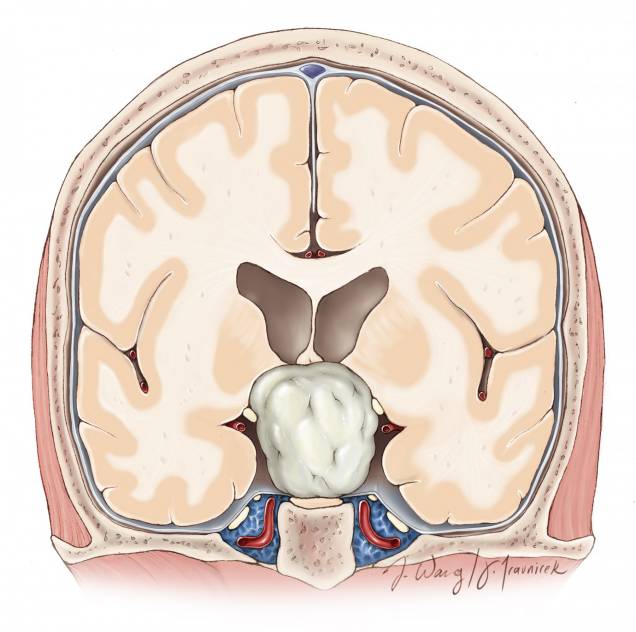

图3. 图示三脑室前部的解剖通道。脑室的大小、因肿瘤所致的室间孔和前脉络裂扩大的程度决定半球间手术通道的侧别。

图4. 如果肿瘤有鞍上黏连和终板池的扩大,则经鼻入路优于经胼胝体入路。复发的肿瘤最好经未受损伤的解剖通道来手术。